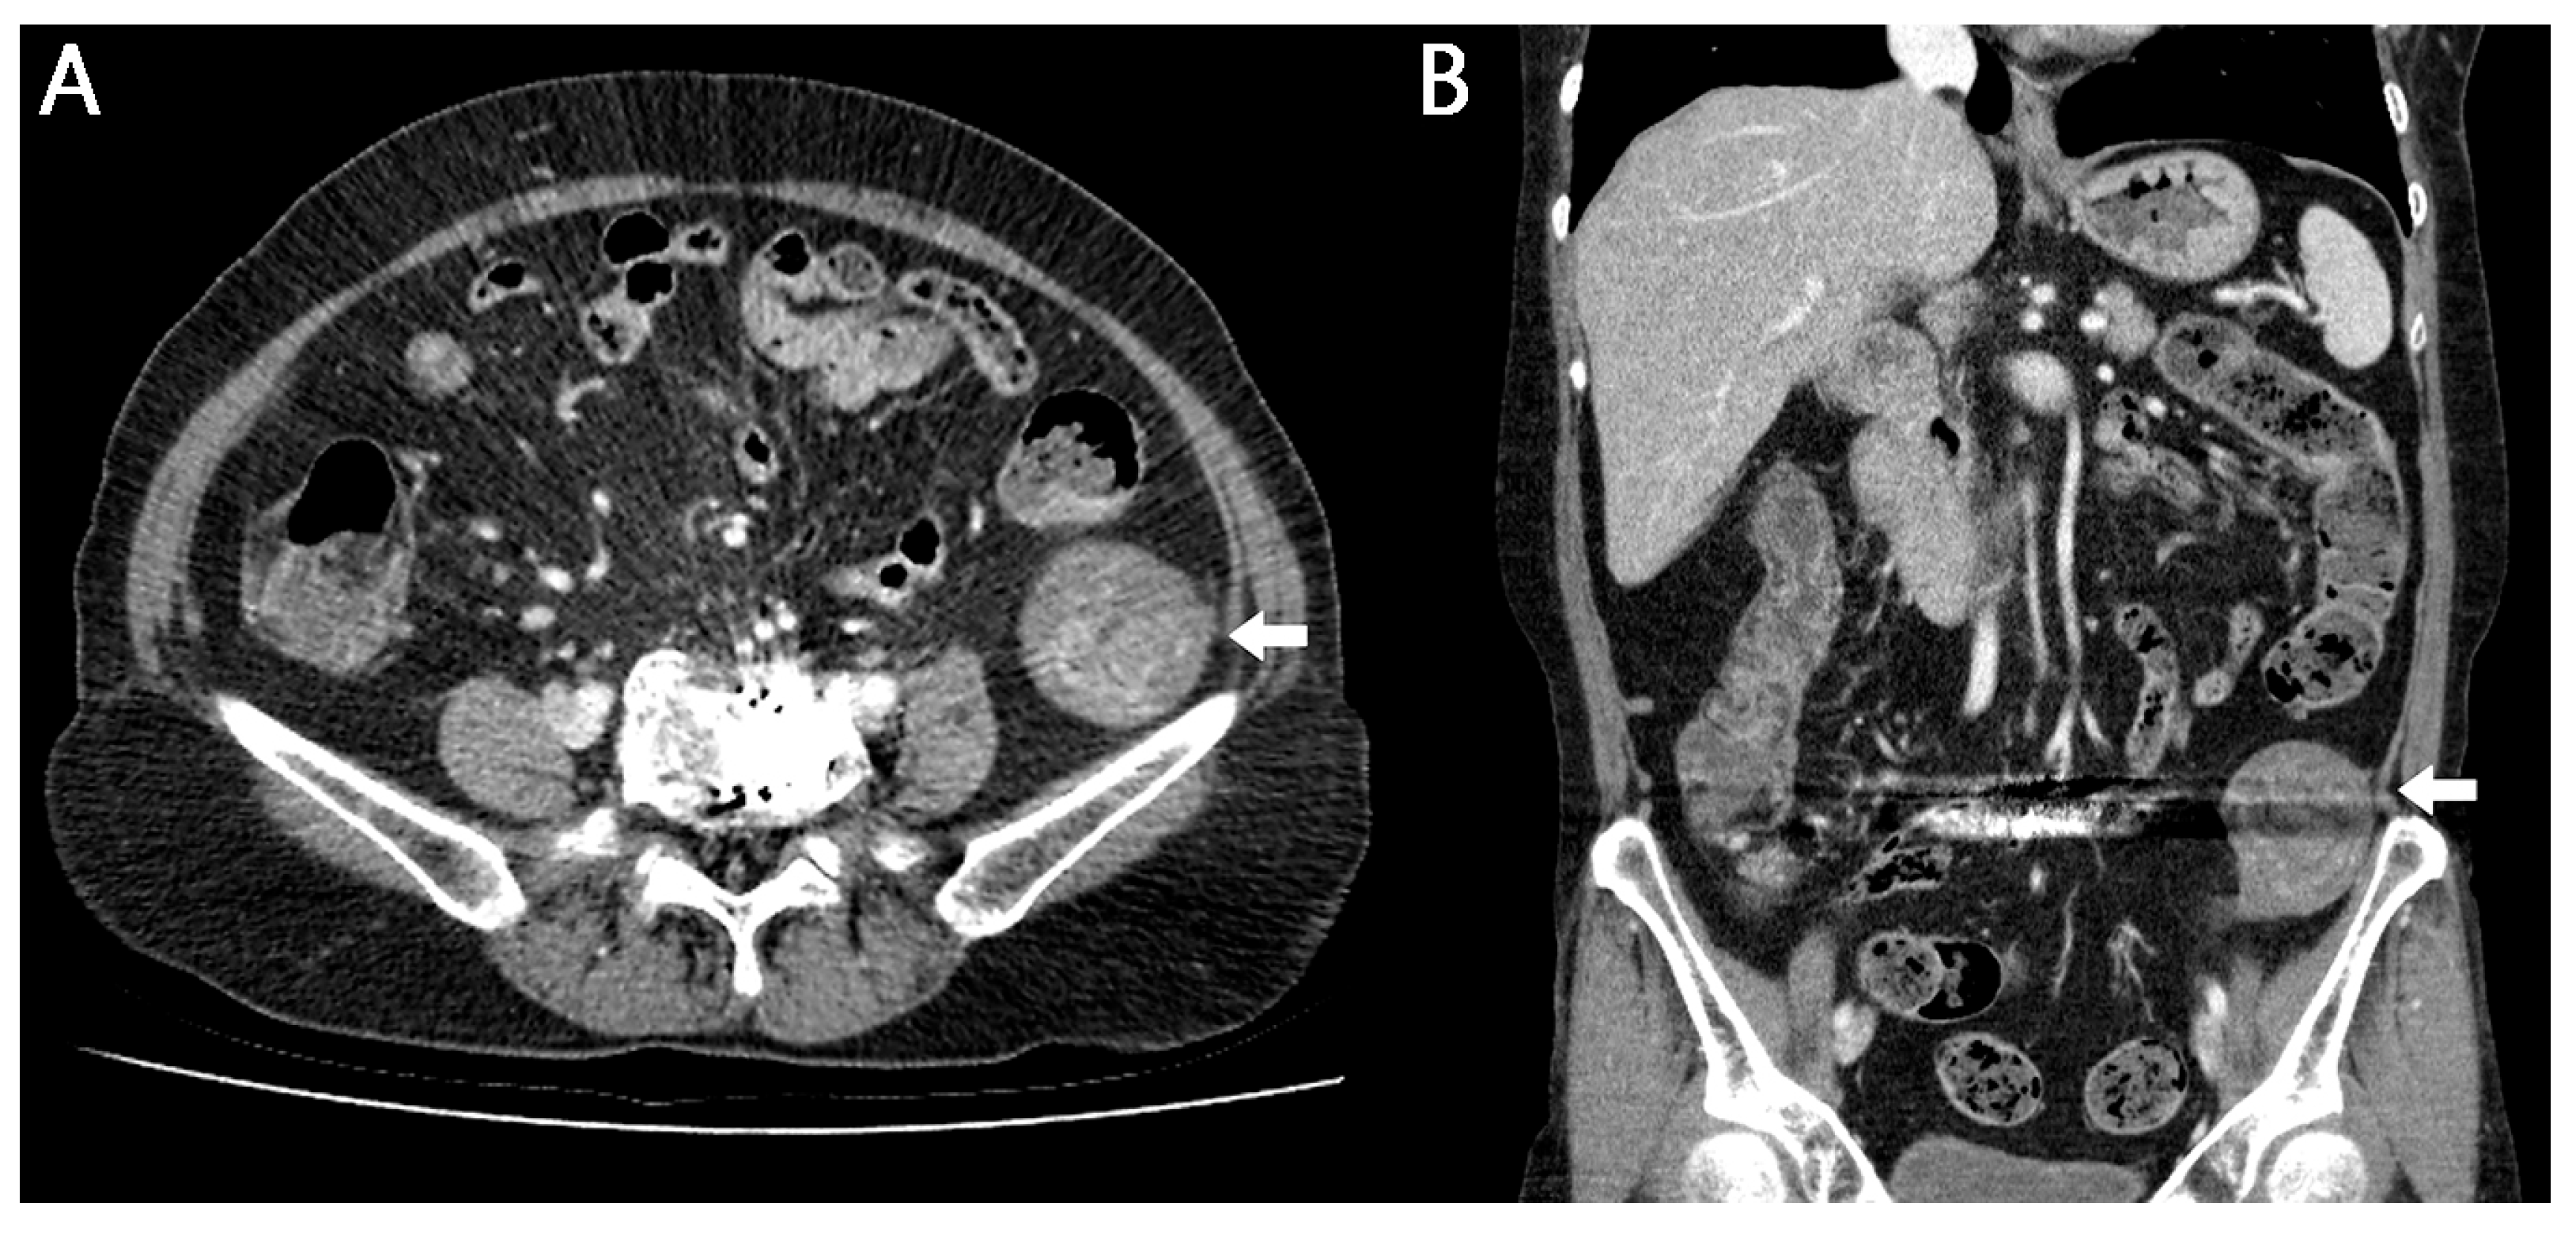

Gossypiboma, a Rare Cause of Abdominal Pain: A Case Report

- Manzella, A.; Filho, P.B.; Albuquerque, E.; Farias, F.; Kaercher, J. Imaging of gossypibomas: Pictorial review. AJR Am. J. Roentgenol. 2009, 193, S94–S101. [Google Scholar] [CrossRef]

- Lu, Y.Y.; Cheung, Y.C.; Ko, S.F.; Ng, S.H. Calcified reticulate rind sign: A characteristic feature of gossypiboma on computed tomography. World J. Gastroenterol. 2005, 11, 4927–4929. [Google Scholar] [CrossRef]